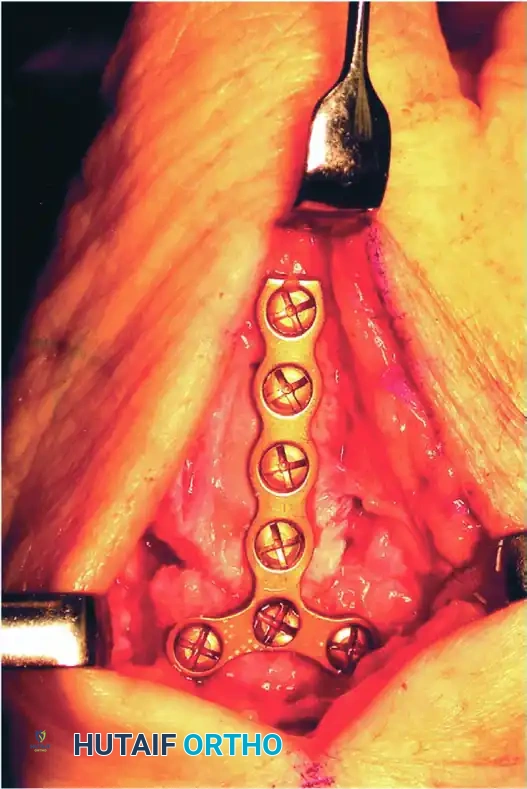

Rigid internal fixation is paramount. The surgeon may choose between plate-and-screw fixation or multiple K-wires, depending on bone quality and surgeon preference.

Option A: Plate Fixation (Preferred for Rigid Stability)

With the provisional K-wire in place, contour a 2.4-mm T-plate or a 2.0-mm/2.4-mm minicondylar blade plate (e.g., Synthes USA, Paoli, PA) to the dorsal-radial aspect of the joint. Insert the screws, ensuring at least two (preferably three) screws achieve bicortical purchase in both the metacarpal and the trapezium.

Take extreme care to use image intensification in multiple planes. It is critical to ensure that the screws or blades do not penetrate the adjacent STT joint or the CMC joint of the index finger.